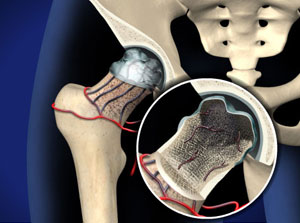

Πρόκειται για μια επώδυνη κατάσταση εξαιτίας της διαταραχής της αιμάτωσης της μηριαίας κεφαλής. Ο επερχόμενος κυτταρικός θάνατος των οστεοκυττάρων τελικά οδηγεί σε καταστροφή της άρθρωσης του ισχίου και αρθρίτιδα. Άλλοι συνώνυμοι όροι που χρησιμοποιούνται για να περιγράψουν την ίδια πάθηση είναι Άσηπτη νέκρωση κεφαλής μηριαίου και Avascular Necrosis of the Hip (AVN). Άσηπτη νέκρωση μπορεί να συμβεί και σε άλλα σημεία του σκελετού αλλά η κεφαλή του μηριαίου οστού και η κεφαλή του βραχιονιού οστού είναι οι συχνότερες εντοπίσεις της νόσου. Σε μερικές περιπτώσεις έχουμε προσβολή και των δύο ισχίων ταυτόχρονα.

Η διαταραχή της αιμάτωσης επιφέρει τον κυτταρικό θάνατο. Το οστό στην κεφαλή του μηριαίου νεκρώνεται και σταδιακά καθιζάνει. Ο χόνδρος που καλύπτει τη μηριαία κεφαλή αποδιοργανώνεται και καταρρέει με αποτέλεσμα τη δημιουργία αρθρίτιδας.